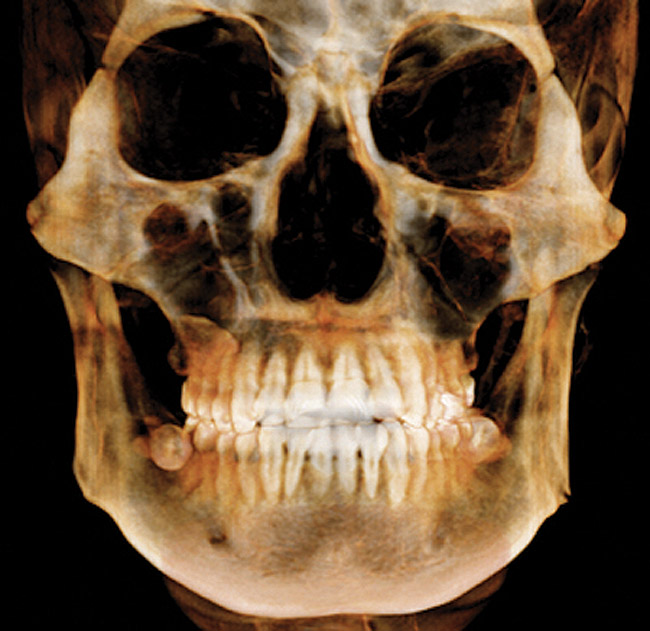

CBCT is indicated for the following: implant planning; developing surgical guides; general observation; finding the correct number of canals in abscessed teeth requiring endodontic treatment; in some cases, for orthodontic planning for patients with asymmetries or who need surgical procedures; for evaluation of impacted teeth or TMJ; and as an adjunct for intraoral imaging. Perhaps the most important CBCT advantage is that it offers a “third dimension” for diagnostic accuracy (Figure 3).22

(3.) CBCT scan showing 3-dimensional rendering of both arches.

Figure 3